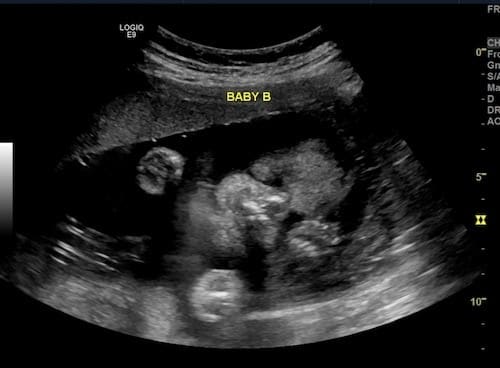

Ultrasound Photos at 25 Weeks Pregnant With Twins